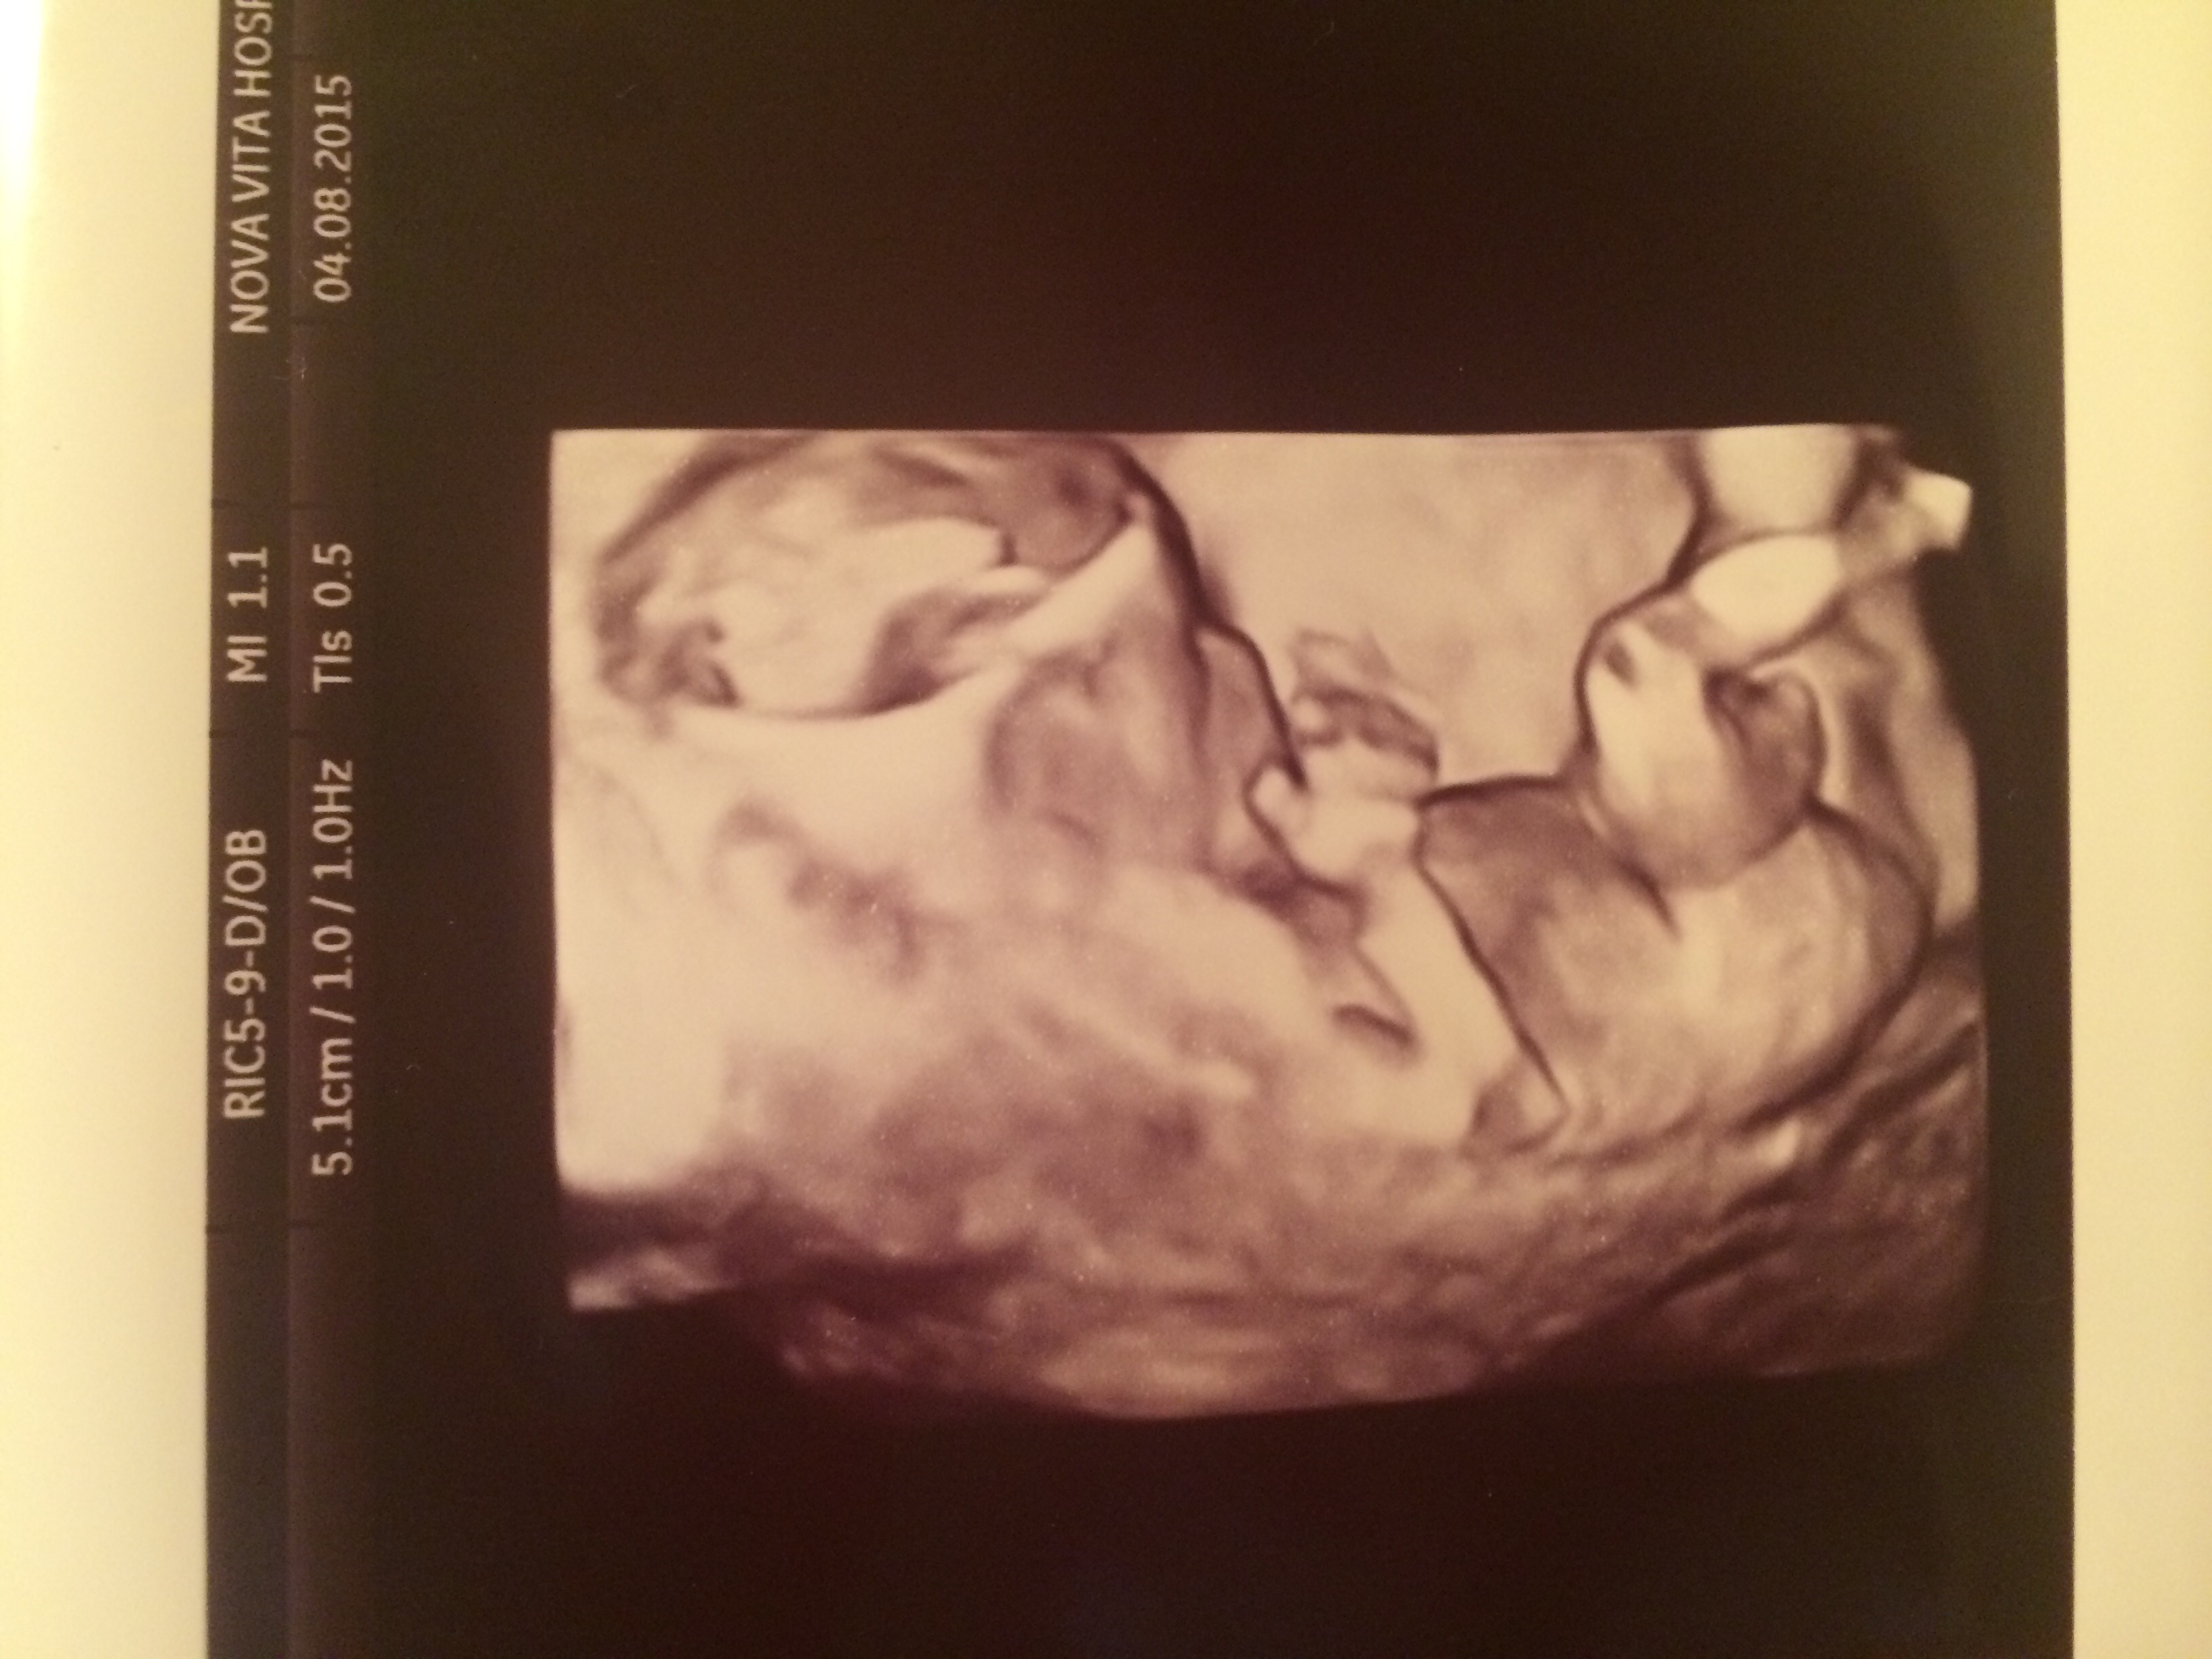

Had our second ultrasound baby was super active and was sucking its thumb ! Heartbeat was 156 Bpm.Ultrasound taken at 12 wks 4 days and today I'm 13 weeks ! Does anyone have a gender guess for my little nugget ? ❤️